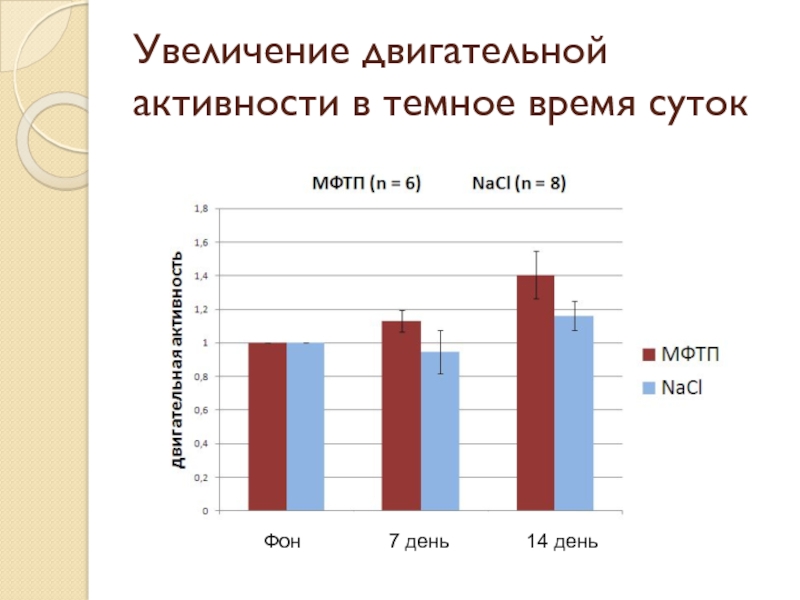

- 19. Увеличение двигательной активности в темное время суток Фон 7 день 14 день

Слайд 20Результаты

Обнаружено уменьшение количества медленного сна и увеличение двигательной активности в темное время суток на 14-ый день после введения МФТП

Обнаружено уменьшение количества медленного сна и увеличение двигательной активности в темное время суток на 14-ый день после введения МФТП